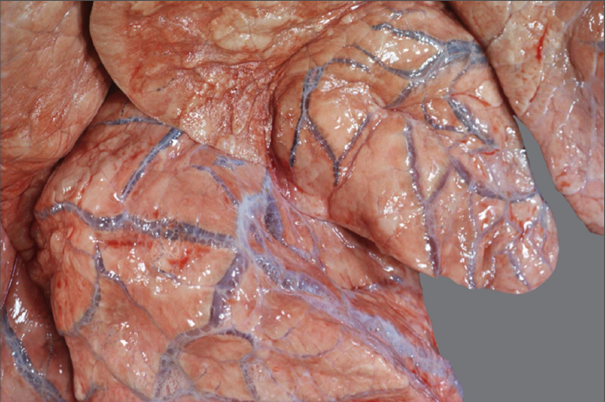

Rind, Lunge: hochgradiges multifokales interstitielles und alveoläres, teils bullöses Lungenemphysem

Beschreibung:

die Lunge erscheint nicht retrahiert

multifokale luftgefüllte Blasen sind im Lungengewebe sichtbar

die Septen erscheinen verbreitert

knisternde, puffige Konsistenz

Hintergrundwissen/ Pathogenese/Ätiologie

- bei ausgeprägter Form bilden sich makroskopisch gut sichtbare Blasen = bullöses Emphysem

- akutes / chronisches Lungenemphysem makroskopisch nicht sicher voneinander abgrenzbar

Alveoläres Emphysem

- Verlegung der luftleitenden Wege mit Ausbildung eines Ventilmechanismus aktive Inspiration bei passiver

Exspiration Luft kann nicht mehr entweichen Lunge bleibt gebläht

- Zerstörung der Alveolen durch langanhaltenden Druck auf die alveolären Kapillaren Mangelversorgung

Atrophie

- Vorkommen:

- Peribronchiolitis (BALT Anbildung)

- Schleim im Lumen, bei Hyperplasie der Becherzellen

- Katarrhalisch-eitrige Bronchitis

- Bronchiolitis obliterans

- allergische Spasmen

- Fremdkörper

Hintergrundwissen/ Pathogenese/Ätiologie

Interstitielles Emphysem

- Zerreißen von Alveolen bei Überblähung

- Vorkommen: Schlachttiere / Euthanasie: Agonal akute Überblähung der Alveolen

links: Kontrolltier rechts: Emphysem

- nicht kollabiert

- glänzende Oberfläche

- hellere Farbe

helles Lungengewebe: alveoläres Emphysem

verbreitere Interstitien: perlschnurartiges Muster -> interstitielles Emphysem